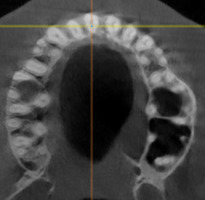

При анализе и описании компьютерной конусно-лучевой томографии (рис. 2а-г) была выявлена генерализованная первичная дегисценция вестибулярной пластинки кости от 1/2 до 3/4 длины корней зубов, зубной ряд целостный, все зубы витальны, кариозных поражений нет. Тип кости 1-2 (Lechkolm и Zarb, 1983), первичная дегисценция вестибулярной костной пластинки превышает пределы возрастной атрофии.

Через 12 месяцев (рис. 7а-г) на срезах компьютерной томограммы 11-ый и 13-ый зубы находятся в костной ткани, при этом костные пики и перегородки укрепились, объем их увеличился; вестибулярно заметен объем костной массы, предположительно компактной формации, исходя из электронной плотности участка. Этим объясняется отсутствие рецидива при лечении рецессии десны как в случае применения аутотрансплантата, также и ТМО (dura mater).